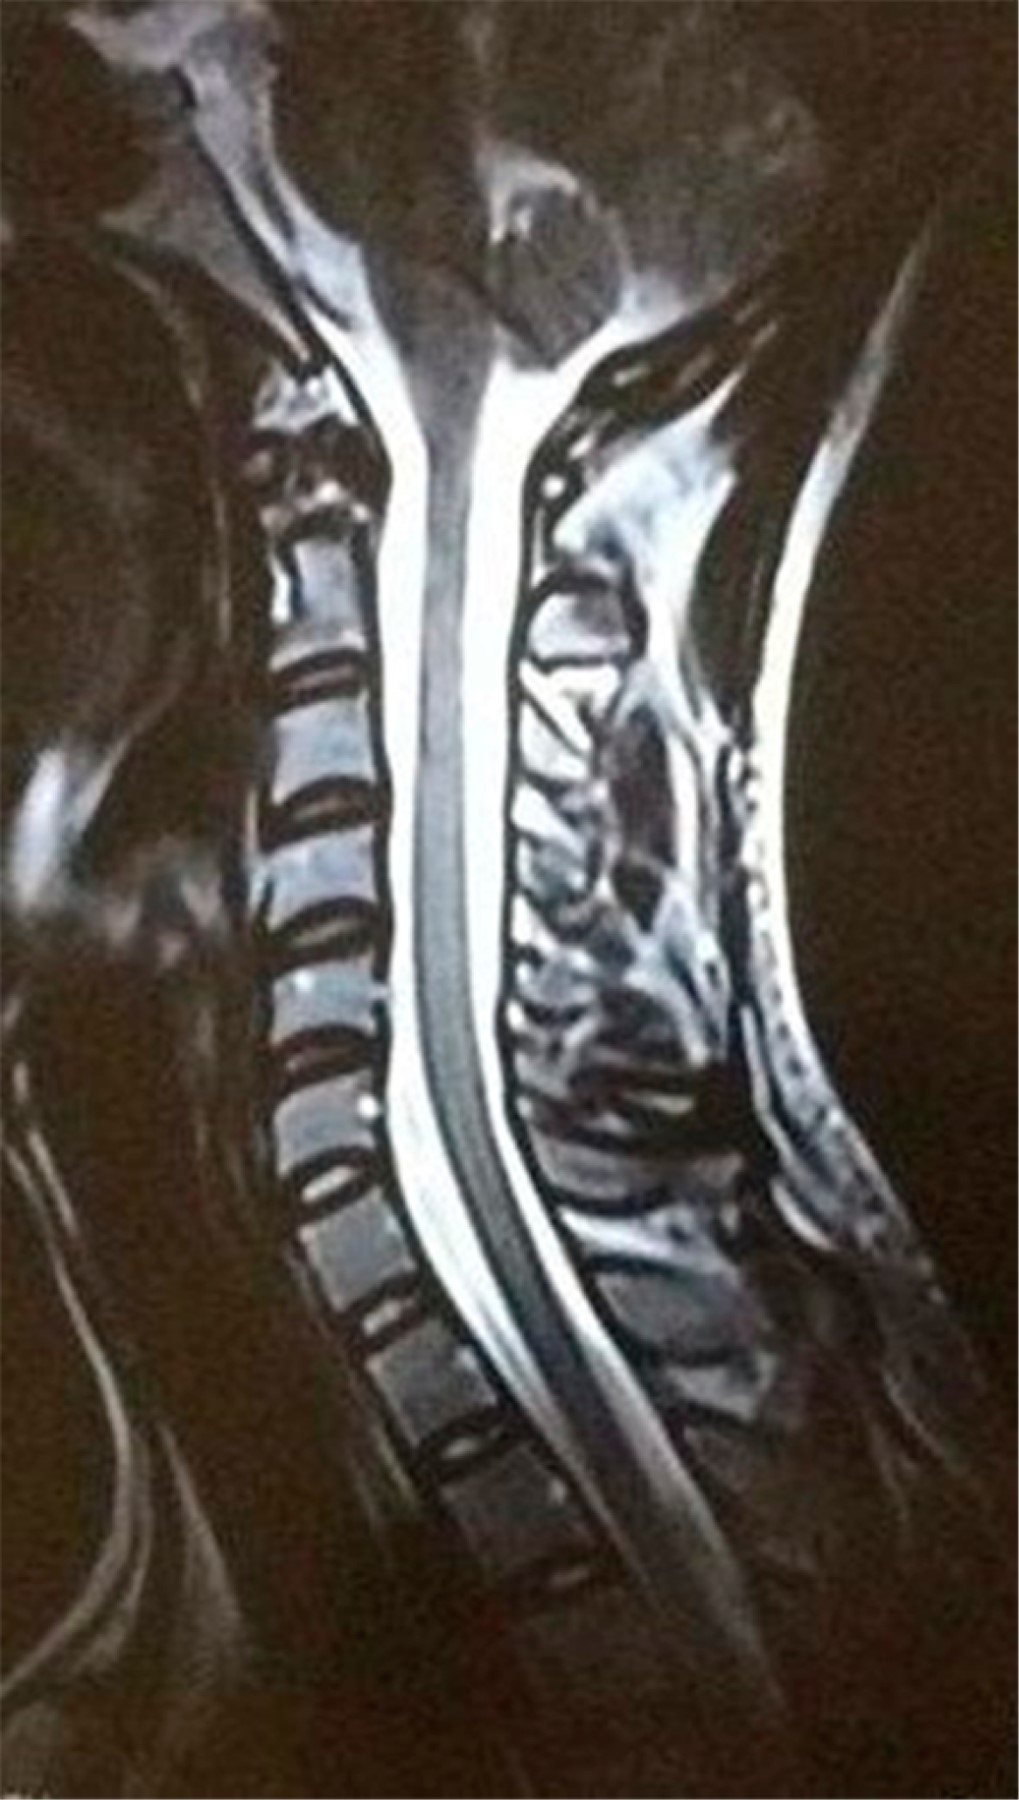

Es valorado por los servicios de neurología y neurocirugía descartando tratamiento quirúrgico. Tres días después se encuentra paciente con evolución clínica favorable, con funciones mentales superiores normales, debilidad distal en extremidades, escala Daniels 4/5, Hoffman y Trommer positivos, reflejos osteotendinosos aumentados en miembros inferiores; Babinski, Chaddock y Gordon ausentes; con adecuada diuresis. Se decide continuar con esteroides IV y se realiza resonancia magnética simple con resultados de pérdida de la lordosis cervical; sin presencia de alteraciones que condicionen compromiso de cordón medular o alguna otra anormalidad (Figura 1). Se concluyó diagnóstico clínico de SCIWORA asociado a Sx de Brown Séquard.

Figura 1